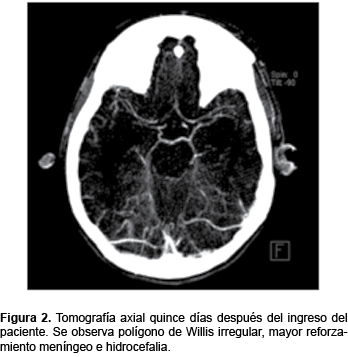

La tomografía inicial de cráneo con asimetría en puente e hipodensidad a nivel mesencefálico con un sistema ventricular normal. Al usar contraste se observó una imagen hiperdensa y reforzamiento de meninges en la tienda, con una relación de sustancia gris y blanca adecuada. El polígono de Willis se reporta normal (Figura 1). Catorce días después de realiza una nueva TAC encontrando polígono de Willis irregular, mayor reforzamiento meníngeo e hidrocefalia (Figura 2). Un mes después de su ingreso se observó la pérdida de la relación de sustancia gris y blanca, con borramiento de circunvoluciones frontales y parietales, reforzamiento meníngeo, así como múltiples áreas hipodensas con disminución de la perfusión cerebral.

Dilatación del sistema ventricular supra e infratentorial ya evidente en el estudio previo. Con la inyección del medio de contraste se apreció la adecuada conformación del polígono, con aspecto arrosariado en las arterias cerebrales medias y anteriores. En el parénquima cerebral no se observaron alteraciones (Figura 2).